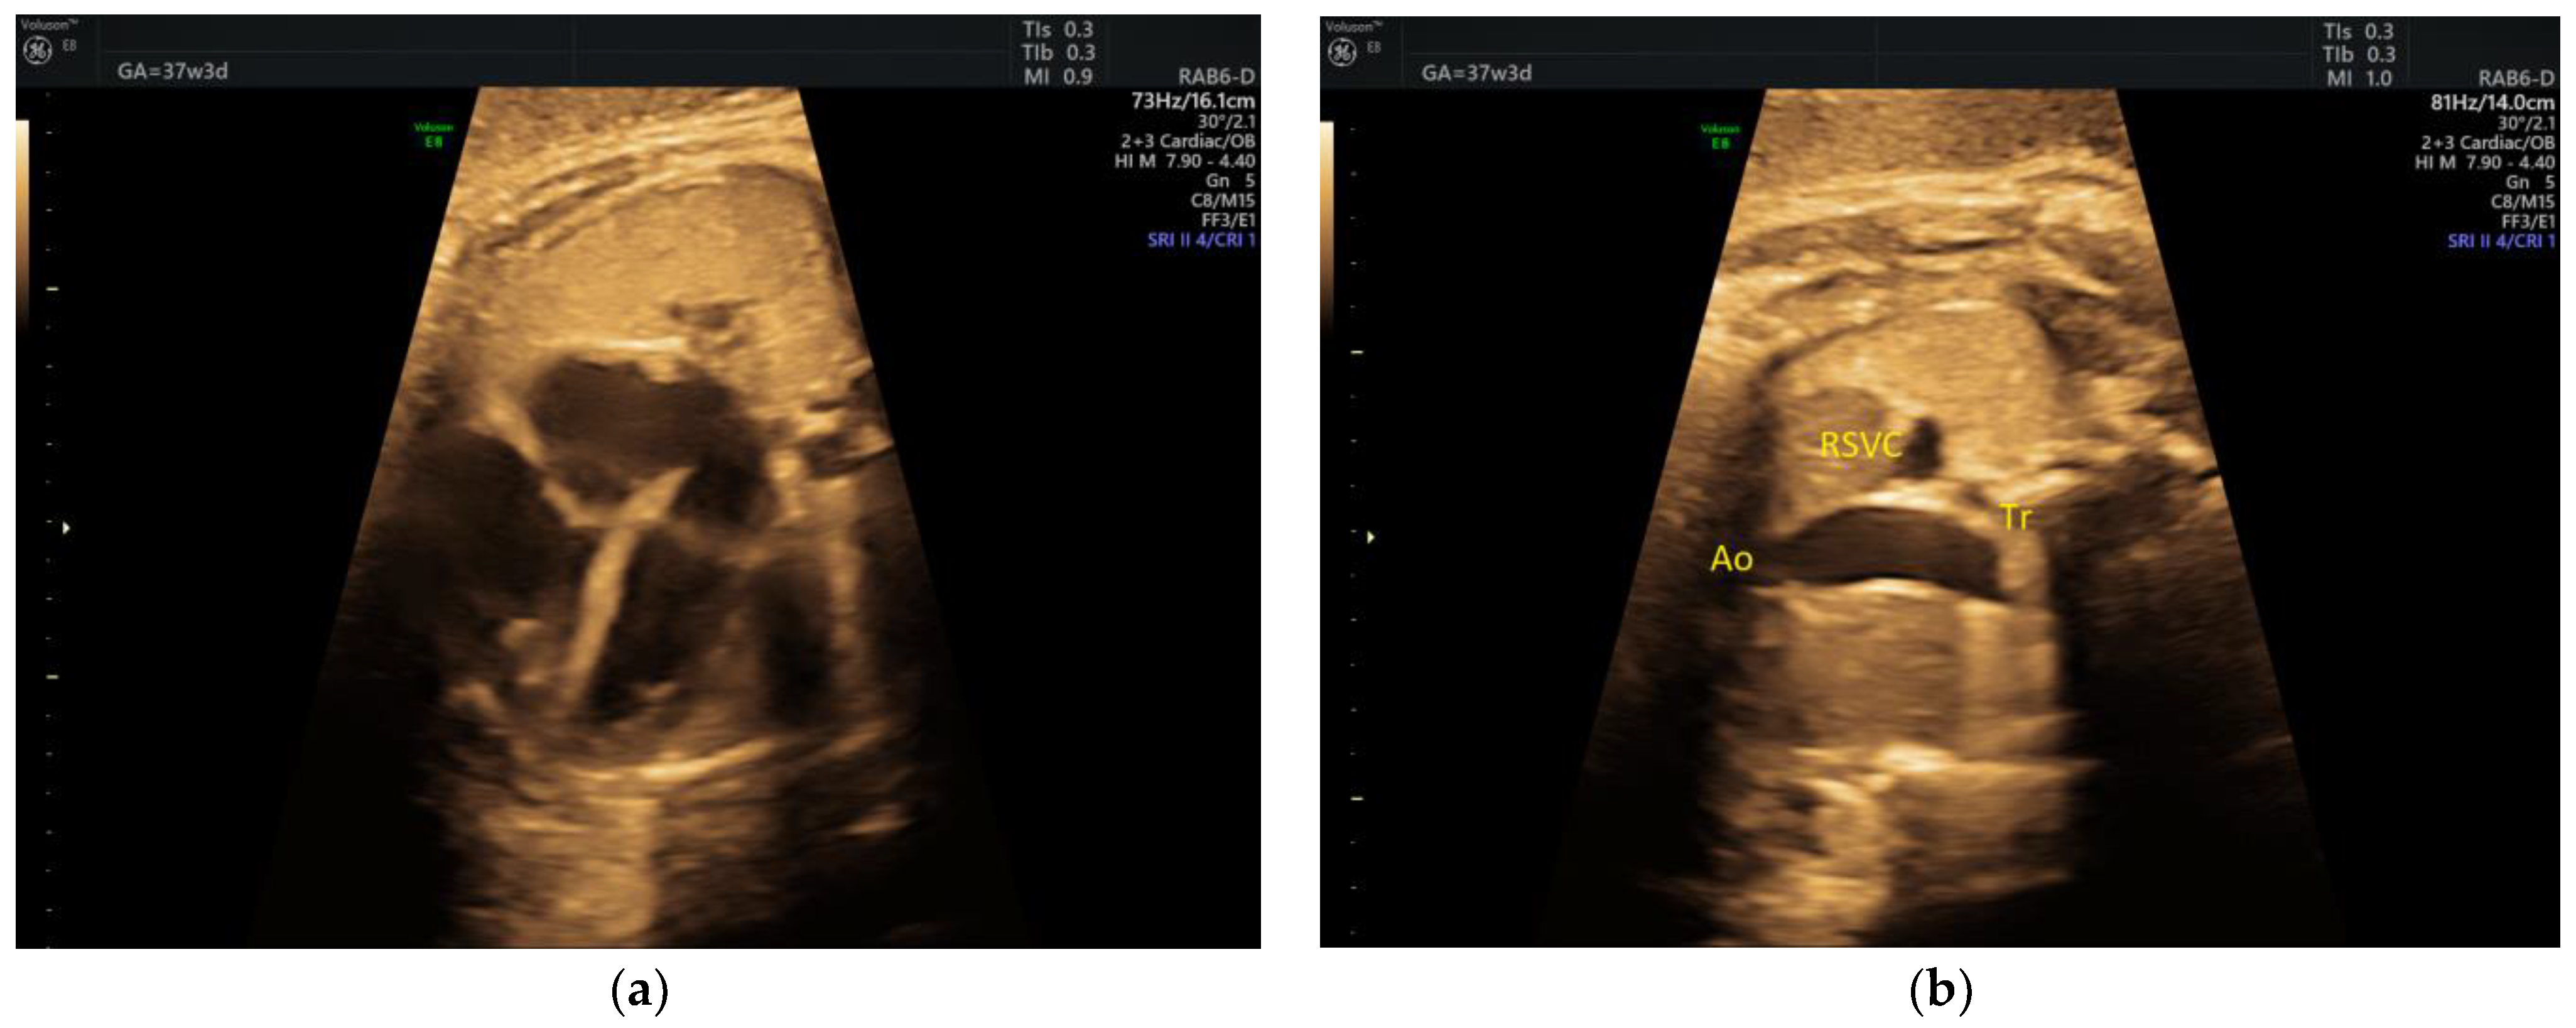

| IAoA | 1 | perimembranous VSD | - | 3VT | + | 0 | 1 | 0 | 1/1 |